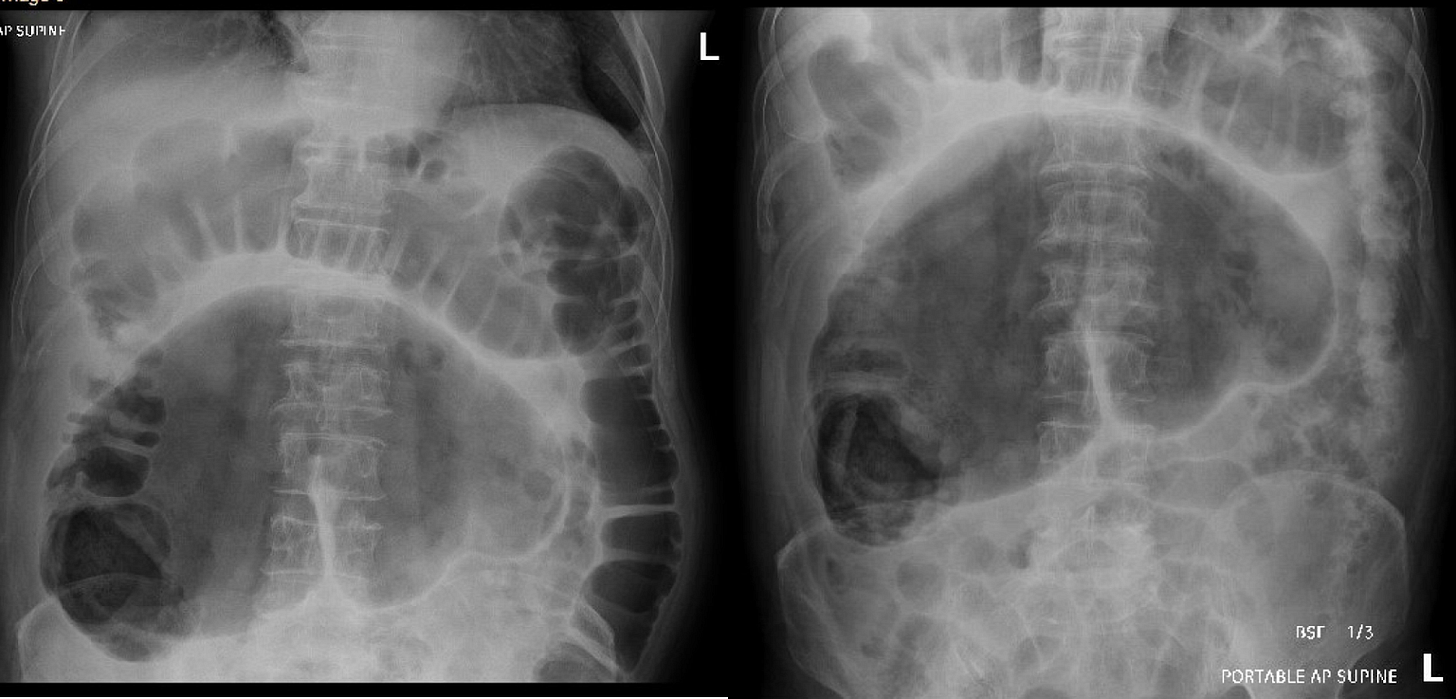

A 61-year-old male with a past medical history significant for DVT/PE on Eliquis and HTN presented to the emergency room after a questionable syncopal episode and a ground level fall. He was found to have a right orbital fracture as well as T8 and L2 vertebral fractures. GI was consulted for abdominal distention, LUQ abdominal pain. A CT abdomen/pelvis showed a distended gallbladder with wall thickening suspicious for acute cholecystitis, L2 acute compression fracture, bilobed abdominal aortic aneurysm, and distention of right and transverse colon. An abdominal ultrasound was done at that time as well showing an abnormal gallbladder with distention and wall thickening, which was suspicious for acalculous cholecystitis. HIDA scan was normal at that time. A KUB was obtained a few days later showing non-dilated small bowel loops, moderate air distention of transverse and descending colon, marked air distention of cecum suspicious for cecal ileus (A, B).

Cecal volvulus occurs because of the cecum twisting around its mesentery, often leading to a bowel obstruction (1). If unrecognized and untreated cecal volvulus can lead to bowel perforation and fecal peritonitis (1). Cecal volvulus accounts for roughly 10% of volvulus cases and typically occurs in younger patients compared to sigmoid volvulus (1). Patients with a developmental failure of peritoneal fixation of the proximal colon and restriction of bowel movement at fixed point from prior adhesions, mass, or scarring are risk factors for development of cecal volvulus (1). On KUB you will typically see marked distention of a loop of large bowel extending from the RLQ to the epigastric area or LUQ which can resemble a coffee bean, as seen above in figures A/B. A contrast enema or abdominal CT scan can be done for further characterization. Treatment options depend on the presence of colonic ischemia and tissue viability (1). In cases where the cecum is not viable a right hemicolectomy is indicated (1). In cases where there is no tissue ischemia treatment involves laparoscopic reduction or colonoscope reduction for patients that cannot tolerate surgery (1). However reduction alone is associated with a high risk of recurrence so cecopexy which involves attaching the cecum to the bowel wall is recommended (1).